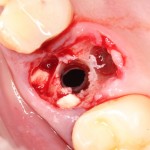

Нам лишь остается заполнить образовавшееся субантральное пространство графтом (Bio-Oss) и закончить операцию синуслифтинга и остеопластики так, как мы планировали:

Минус этого варианта в том, что коллагеновая матрица Mucograft сравнимых с барьерной мембраной размеров, например, 15х20 мм, стоит дороже. К тому же, сама компания Geistlich не одобряет такой подход, ссылаясь на установленные протоколы и инструкции по применению биоматериалов. Тем не менее, мне он кажется очень удобным и доступным, ведь наибольшее количество перфораций имеют размер менее 5-6 мм, что позволяет легко и относительно недорого перекрывать их с помощью Mucograft Seal 8 mm. Ну и, на мой взгляд, коллагеновая матрица, благодаря своим свойствам, относительно спокойно переживет контакт с микрофлорой верхнечелюстной пазухи и не позволит ей инфицировать подлежащий графт.